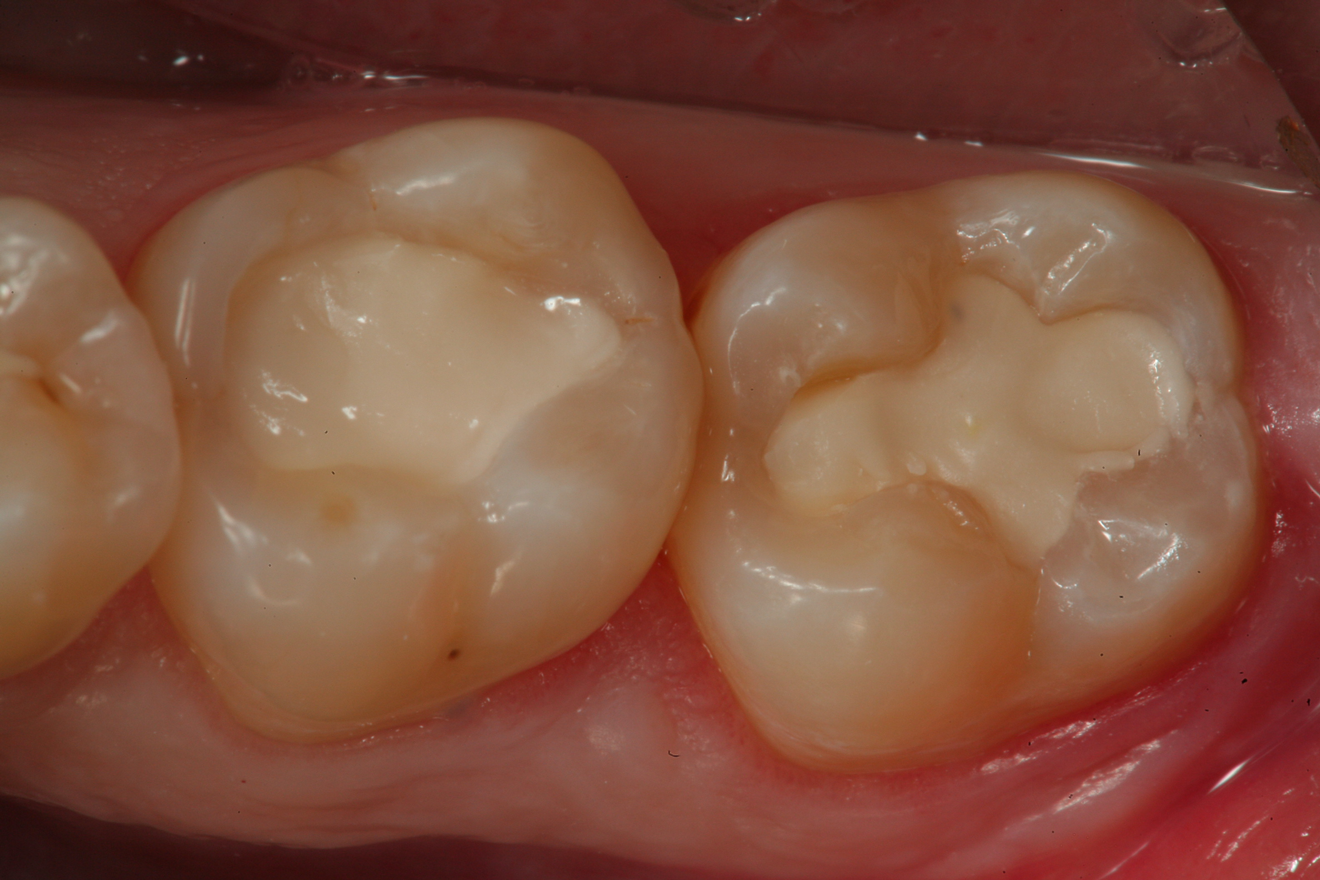

Fig 10. A preoperative occlusal view of tooth Nos. 18 and 19 with composite restorations that are exhibiting marginal breakdown.

Figure 10